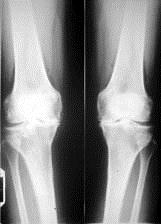

病历摘要: 患者女性,65岁,双膝关节疼痛畸形,伸直受限10分钟,加重3个月。查体:双膝关节呈内翻畸形,双膝关节屈曲90受限,伸直受限,实验室检查正常,癤...

问题 病历摘要: 患者女性,65岁,双膝关节疼痛畸形,伸直受限10分钟,加重3个月。查体:双膝关节呈内翻畸形,双膝关节屈曲90受限,伸直受限,实验室检查正常,癤线见图: 该患者进一步怎么治疗?